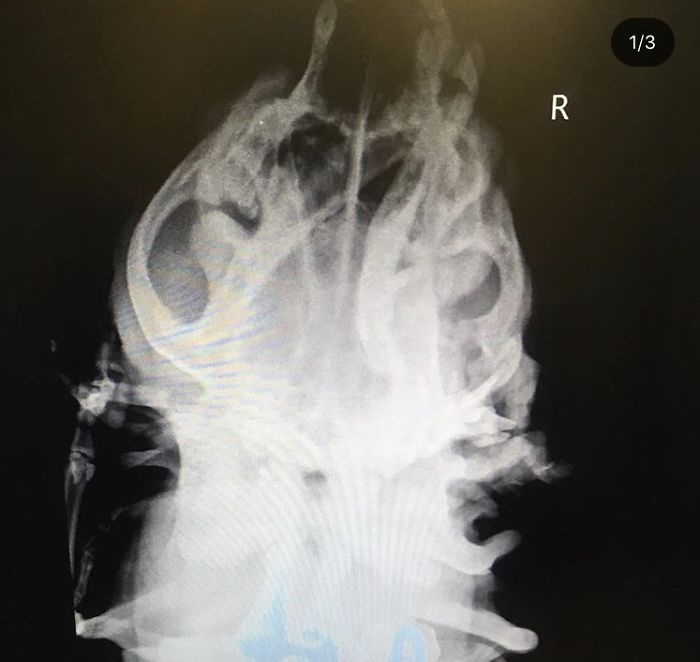

We took more X-rays of Toad’s skull. Now that we have had Toad for a long time and learned about her issues more than when we first met her, we are able to understand the X-rays a bit better. The first image shows how wonky her skull is shaped. She has an extra orbital bone around her eye socket, likely from the skull of the twin she absorbed in utero, which makes her skull extra bulbous. The red circle shows two sets of hyoid bones. The yellow shows how the vertebrae aren’t attached the way they are supposed to be. The green circle shows her extra trachea, which is not fully formed.